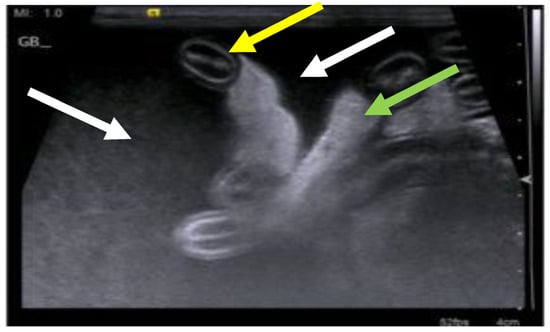

7.4. Diagnostic Imaging in FIP

7.4.1. Routine Imaging: Ultrasonographic and Radiographic Findings

7.4.2. Advanced Imaging of the CNS: MRI and CT

| Summary of Section 7: Diagnosis of FIP; Section 7.4: Diagnostic imaging in FIP: No specific ultrasonographic or radiographic findings exist for FIP. Ultrasonography (in particular) and radiography can show the presence of effusions. Pneumonia due to FIP that is occasionally reported can be associated with radiographic changes. Ultrasonography can reveal abdominal lymphadenomegaly or lymphadenopathy and/or abnormalities of the liver, spleen, intestines and/or kidneys (which can include a medullary rim sign), depending on which organs are affected. Imaging can also be of use to the direct sampling of abnormal tissues, e.g., fine-needle aspirate for cytology examination to reveal non-septic pyogranulomatous inflammation, or ultrasound-guided needle core (e.g., tru-cut) biopsies can be collected and submitted for histopathology. When a cat is showing neurological signs, the imaging of the brain by magnetic resonance imaging, if available, with contrast, can be useful to demonstrate neurological abnormalities (such as obstructive hydrocephalus, syringomyelia, foramen magnum herniation and marked contrast enhancement of the meninges, third ventricle, mesencephalic aqueduct, and brainstem). A description of computerised tomography findings in cats with neurological FIP has not been published, but MRI is likely to be more sensitive in the detection of subtle intraparenchymal lesions. Advanced imaging of the central nervous system is indicated before performing cerebrospinal fluid sampling to assess the potential risk of herniation. |